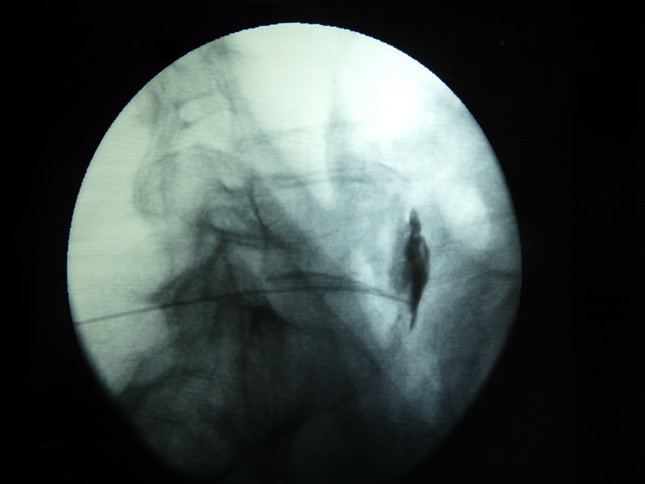

Fig.3. Introducccion de la aguja de Chiba en dirección perpendicular a la piel en el espacio intralaminar L5-S1, en proyección AP, esta se introduce en dirección al disco intervertebral penetrando al saco tecal lo cual se realiza en proyección lateral.

4/6